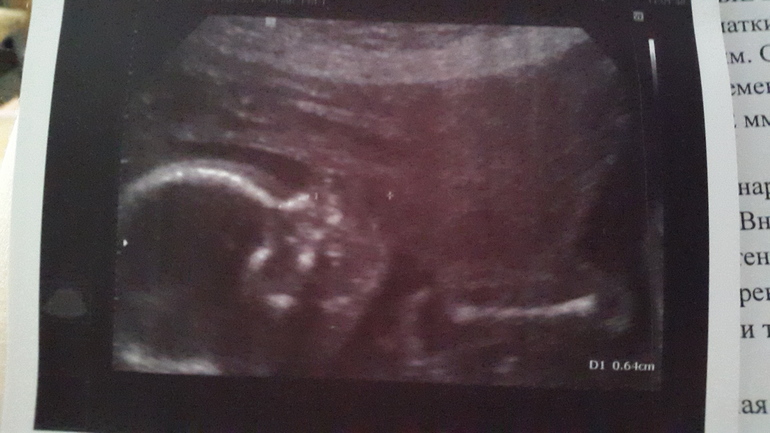

Узи 21-а неделя и узнала пол😊

Доплер Сходила на УЗИ....